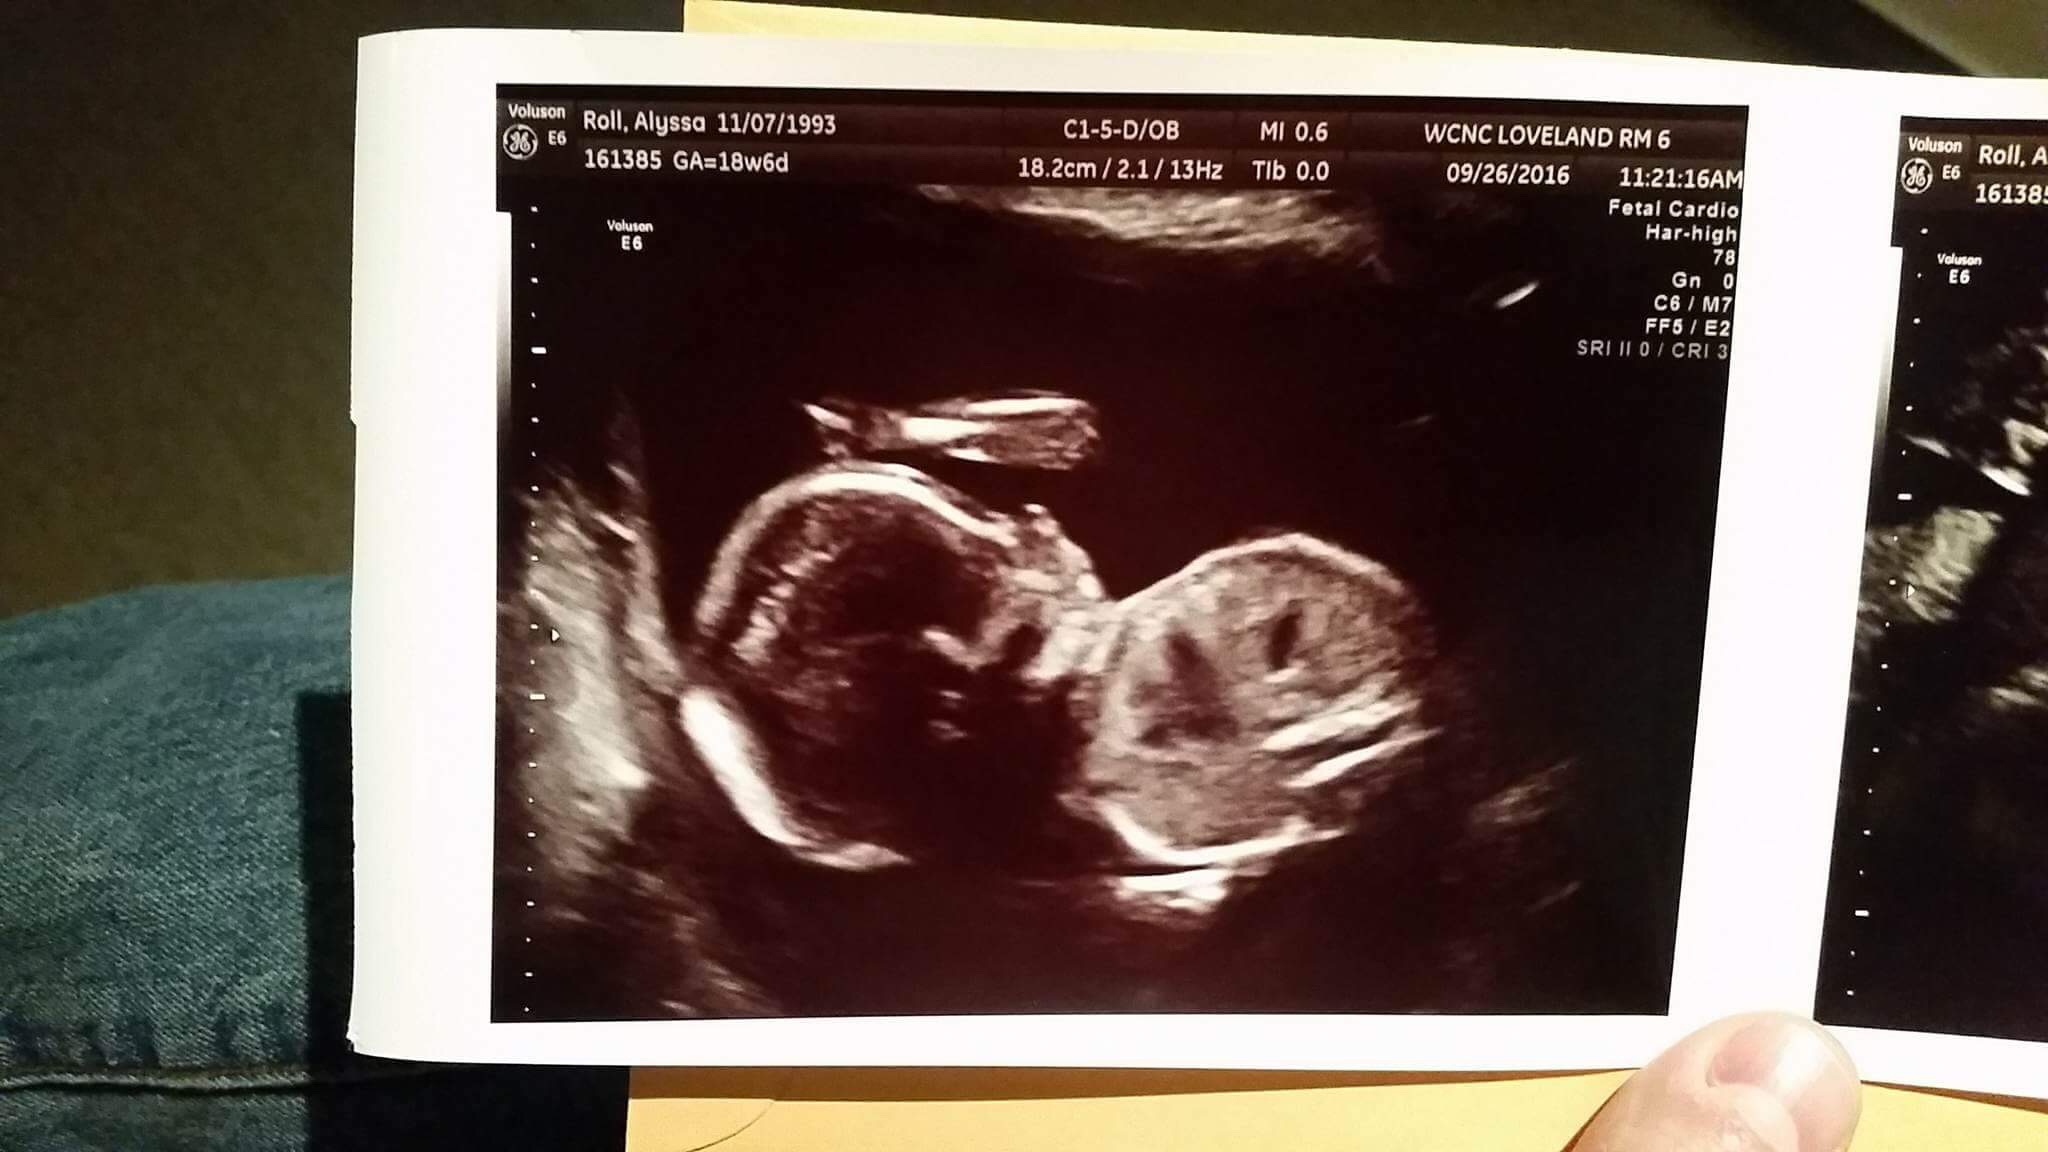

This is an ultrasound picture of my first nephew, Jameson. He was born on February 15, 2017 to my sister and her husband. Every time my wife and I receive a new picture of Jameson, or whenever we get to visit, he changes so much and so quickly.